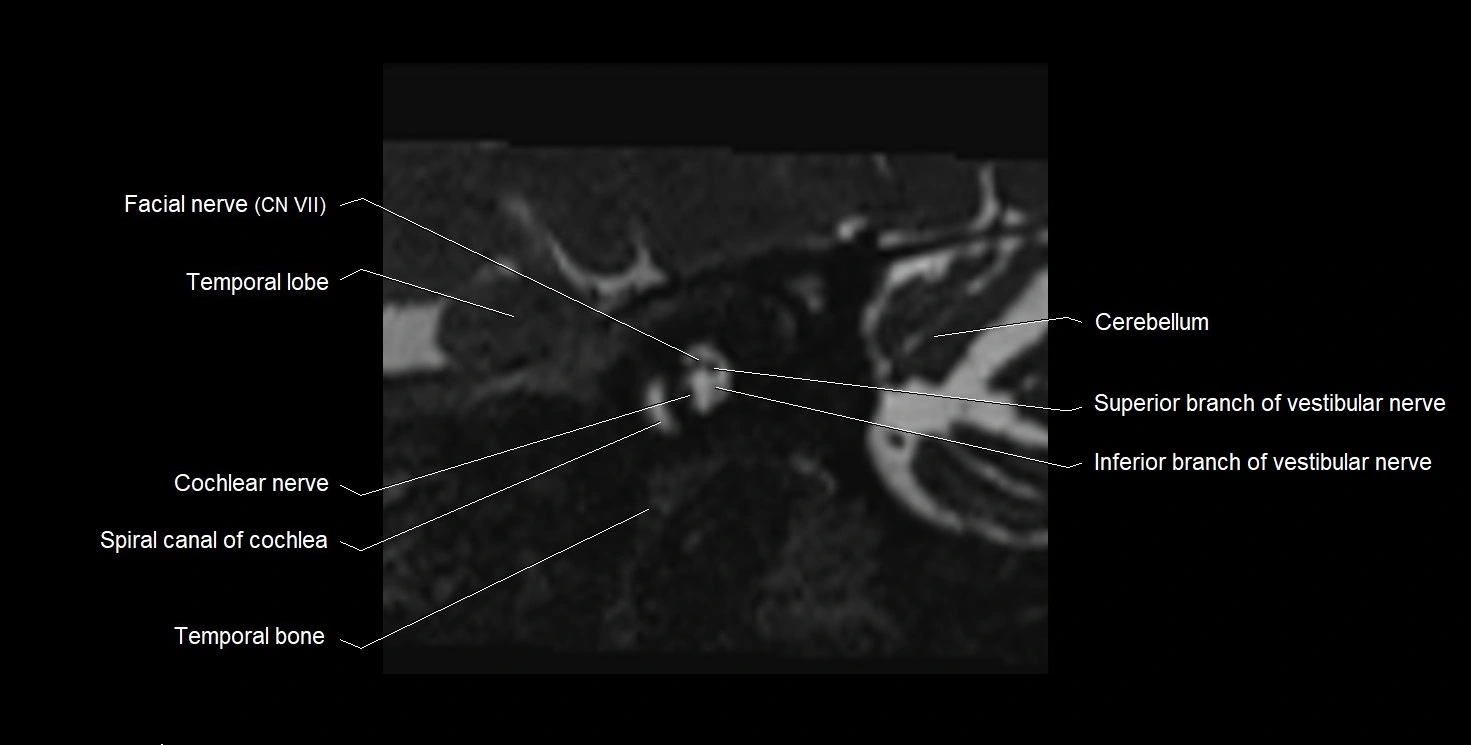

MRI Appearance

• The abducens nerve is a small, thin, linear structure

• Best visualized on high-resolution T2-weighted 3D MRI sequences (e.g., FIESTA or CISS)

• Seen as a hypointense (dark) line running from the brainstem at the pontomedullary junction, traversing the prepontine cistern, and entering Dorello’s canal under the petrosphenoidal ligament, then into the cavernous sinus, and finally the orbit

• May be challenging to visualize in standard MRI due to its small size

• Pathology may be inferred by absence, displacement, or enhancement of the nerve